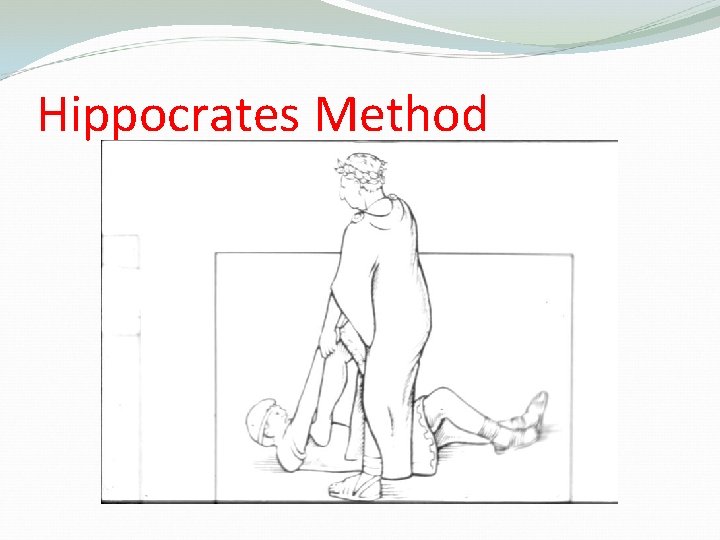

Methods of Reduction of anterior shoulder Dislocation Hippocrates Method ( A form of anesthesia or pain abolishing is required ) Stimpson’s technique ( some sedation and analgesia are used but No anesthesia is required ) Kocher’s technique is the method used in hospitals under general anesthesia and muscle relaxation

Hippocrates Method